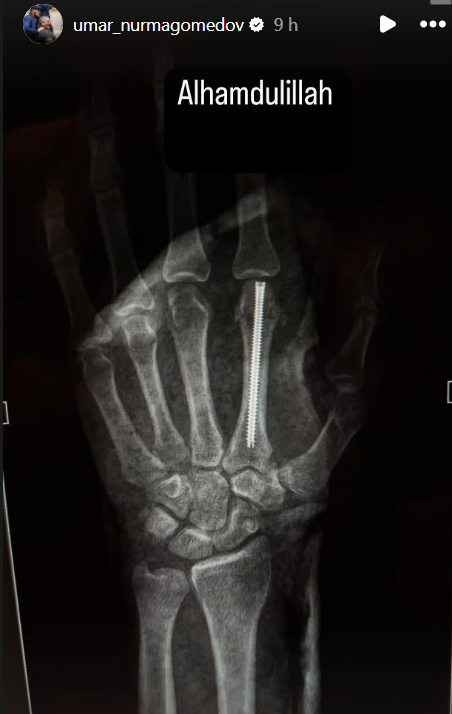

A lesão sofrida por Umar Nurmagomedov na derrota para Merab Dvalishvili no ‘co-main event’ do UFC 311, no último sábado (18), levou o russo à mesa de cirurgia. Nesta quinta-feira (23), o peso-galo (61 kg) utilizou suas redes sociais para publicar uma imagem de raio-x da sua mão esquerda após passar pela operação (veja abaixo).

Na imagem, é possível ver que, durante a cirurgia reparadora, foi introduzido um parafuso no osso metacarpo do dedo indicador da mão esquerda do lutador. A fratura, de acordo com a equipe de Nurmagomedov e com o próprio atleta, teria ocorrido ainda no começo da luta contra o campeão Merab Dvalishvili.